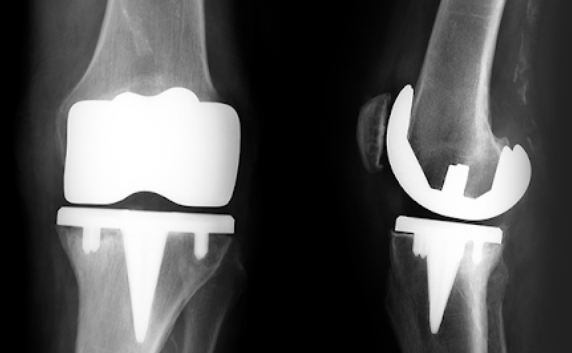

무릎 인공관절 수술은 퇴행성 관절염이나 관절 손상으로 인해 정상적인 생활이 어려운 분들을 위해 손상된 관절을 금속 또는 플라스틱 인공관절로 치환하는 수술입니다.

- 일반적으로 치환술이라고도 하며, 전치환(전체 교체)과 부분 치환술로 나뉩니다.

7. 무릎 인공관절 수명과 재수술 여부

- 평균 15~20년 수명 (일상생활 기준)

- 50대 중반에 수술할 경우, 80세 전후에 재수술 고려 가능성 있음